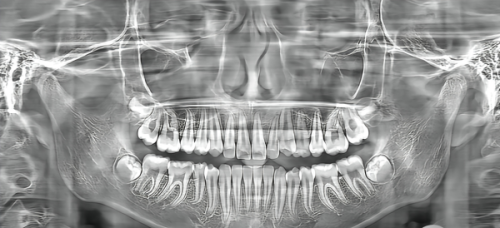

除了专精的医生团队,天津河西美澳(原美奥)口腔还引进了一系列精良的口腔设备。例如,数字化口腔扫描仪可以快速、正确地获取口腔内部的三维图像,为医生制定治疗方案提供详细的数据支持。激光治疗设备可以在治疗过程中减少患者的痛苦,提高治疗效率。这些精良的设备不仅提升了治疗的精细度和安心性,还让患者在治疗过程中感受到更加舒适的体验。